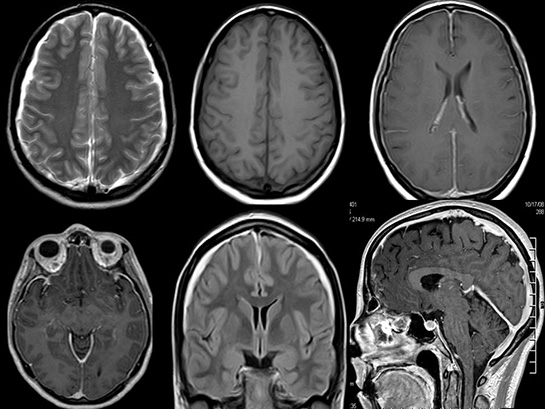

Tanı Yöntemleri Beyin sapı tümörlerinin tanısı, genellikle aşağıdaki yöntemlerle konulur: